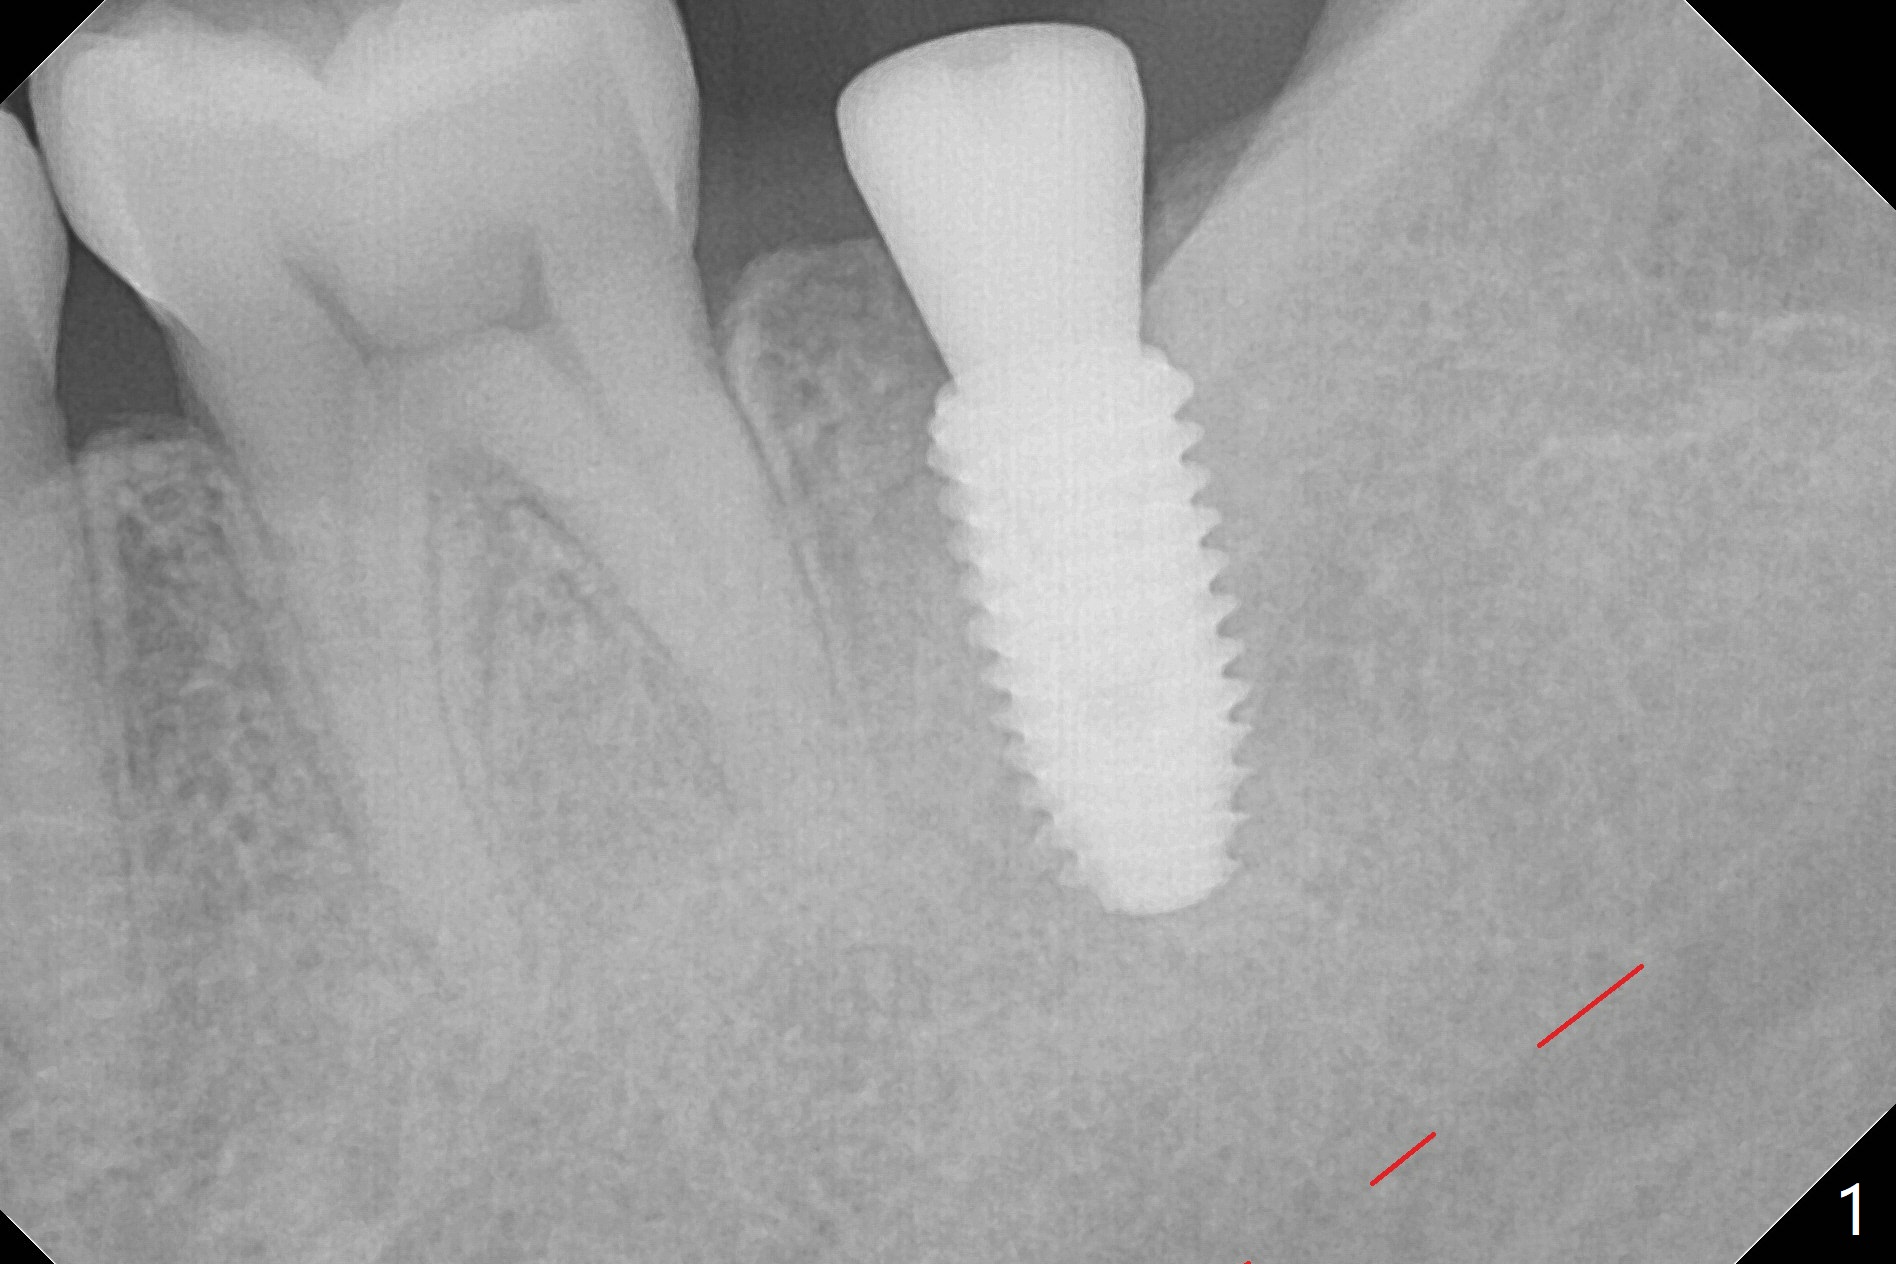

As usual, one ampule of 2% Xylocaine with 1:100,000 Epinephrine provides profound anesthesia and hemostasis at the site of #18. A 5x10 mm implant is placed with guided surgery in ~10 minutes. A shortage is low stability (10 Ncm), probably due to low bone density, which is not detected early (with increasing drill diameters). When a 5 mm tap is being used, there is basically no resistance. In fact the tap should be not used. When a 5.5x5 mm healing abutment is placed, hemostasis is achieved (Fig.1). There is sufficient clearance from the Inferior Alveolar Canal (red dashed line). More important is there is no risk of perforation of the lingual (L) plate as by design (Fig.2). There is no reported postop pain. There is no bone loss around the implant 3.5 months postop, which suggests that it is an atraumatic procedure (Fig.3). The all-purpose guide also allows neutral placement of the implant buccolingually (Fig.4), as compared to the partial one.